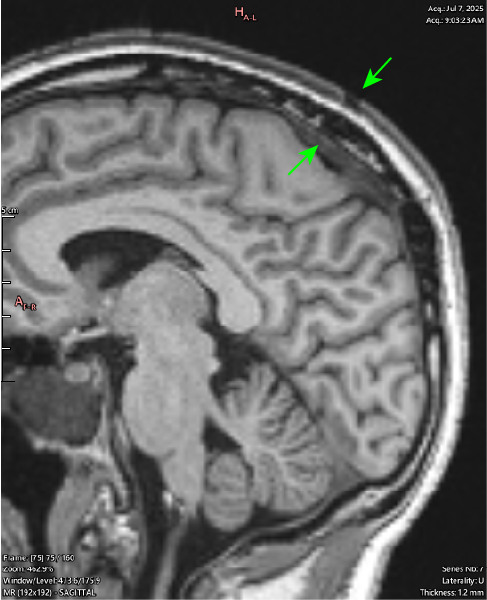

T1 Sagittal

The same slice shown above (right), with a wider window setting to better demonstrate what is actively happening in this area.

There is hypointense soft tissue signal throughout the areas of skull destruction, including in the cortical layer of the skull (black signal out table of the bone). This demonstrates an active pathological process of osteolysis occurring, in which the bone is destroyed and replaced by this tissue.